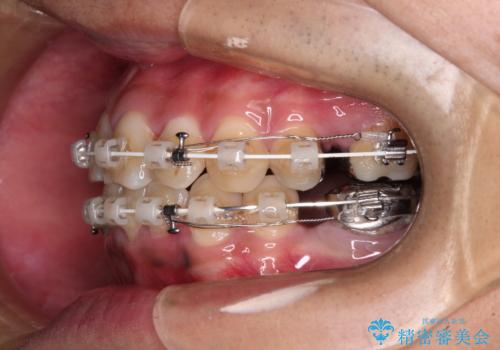

重なって磨きにくい上下の前歯 ワイヤー装置での抜歯矯正

- 前歯のデコボコを改善したいと来院された患者様です。

口元の突出感はないものの、上顎前歯のデコボコが著しかったため、上下顎左右小臼歯4本を抜歯することとしました。

上下の正中位置を改善するため、右下は第一小臼歯を、その他は第二小臼歯を抜歯することとしました。

第二小臼歯抜歯の矯正治療は、治療期間が長引くことが多いですが、動きが非常に良く、予定の治療期間で終えることができました。

上下の正中も思っていた以上に良い位置に改善されました。